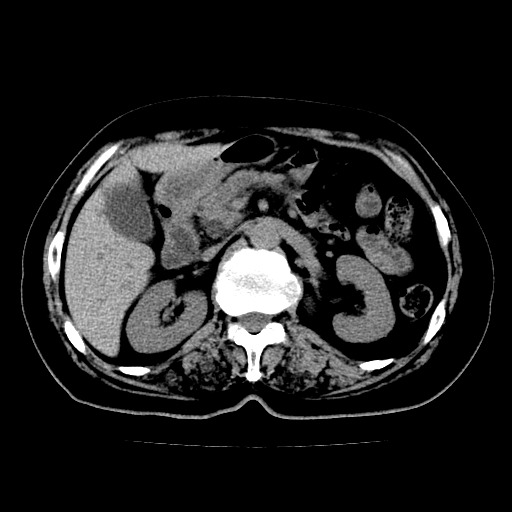

以下是引用lujiandong在2009-2-8 9:37:00的发言:[br]从所发的ct平扫图象上看,胆总管明显增粗,从上向下逐渐变细,是否有泥沙样结石,建议薄层重建;胰腺形态基本正常,左侧肾前筋膜轻度增厚。可以考虑:轻度单纯性胰腺炎,建议ct增强扫描。